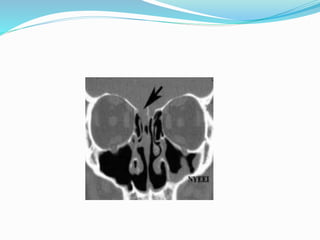

 2.Radiological tests: to localize the site of defect.

 HRCT,

 MRI for active leaks and in cases of encephalocele and

SOL.

 CT cisternogram: It requires intra thecal inj of

iohexol dye and CT to localise the site.

Laboratory Tests:  1.Immuno electrophoretic demonstration of beta 2 transferrin is the diagnostic test.  Beta 2 transferrin is a protein seen in CSF . Its presence is a specific and sensitive for CSF. Perilymph and aqueous humour are the only other 2 fluids than CSF that contain this protein  2.Radiological tests: to localize the site of defect.  HRCT,  MRI for active leaks and in cases of encephalocele and SOL.  CT cisternogram: It requires intra thecal inj of iohexol dye and CT to localise the site.